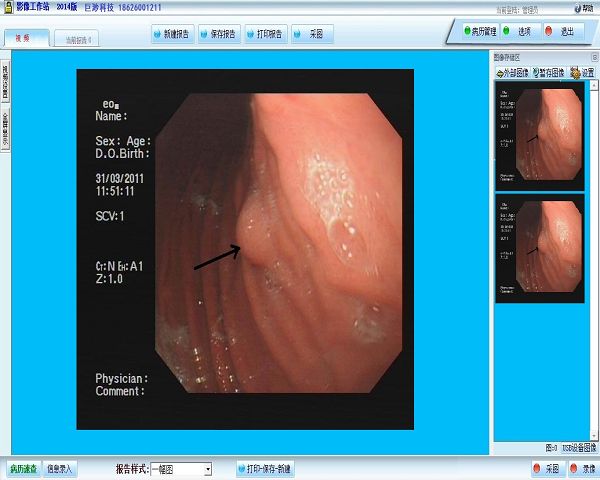

影像工作站 病理图文分析系统 检影验光显像系统软件 内窥镜影像工作站 支气管镜影像工作站 腹腔镜影像工作站 检验图文影像管理系统软件 宫腔镜影像工作站 肠镜影像工作站 膀胱镜影像工作站